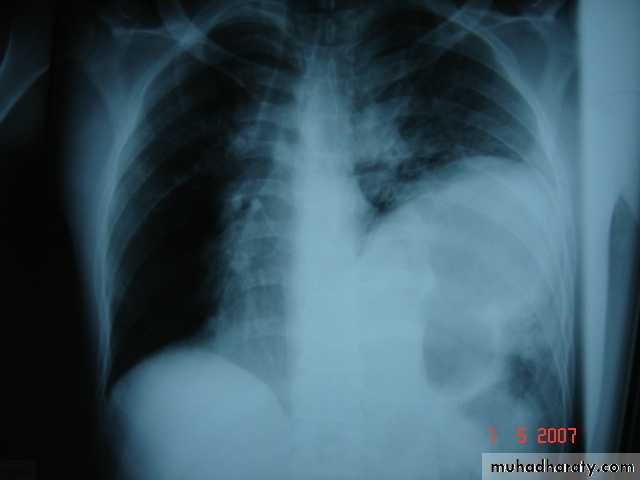

• Pulmonary Echinococcosis (Hydatid Cyst)

• Hydatid disease of the lung is caused by the small tape worm (Taenia Echinococcus ) or (Echinococcus Granulosis) .Hydatid cyst means cyst full of water .It has a life cycle between dogs & sheep .Parasites in the elementary tract of the dog shed ova that excreted in the dog faeces , contaminated the food of the sheep in which hydatid cyst will develops in the viscera . Including the lung .Infected sheep when slaughtered and its entrails are eaten by dogs , the life cycle is completed .When a human being hands or food become contaminated with canine fecal material containing ova which will be ingested .The parasitic larva burrow through the gastric mucosa and are carried to the liver in the portal venous circulation where most of them filtered out to form hydatid cyst of the liver , some escape the liver & lodge in the lung to form one or more hydatid cyst which grows slowly or rapidly over years .

• The cyst consists of a germinal layer & cyst fluid containing broad capsule & scoleses . A cellular white hyaline layers are laid down outside the cyst so that the cyst is enclosed by a laminated cyst membrane .As the cyst enlarged , it usually reaches the pleural surface . Compression of the lung tissues produces a thin fibrous layer of atelectatic lung tissue around the cyst (capsule , pericyst or adventia)

• A-Asymptomatic• Any smooth homogenous opacity of uniform density with clear cut border and little or no reaction around it on a chest X-Ray is a hydatid cyst unless proved the other wise .

• Radiological Findings

• 1-Smooth homogenous opacity (Intact H.C).• 2-Partial rupture (per vesicular pneumocyst).

• 3-Complete rupture (Water –lilly sign) .

• 4-Formation of lung abscess(Air –fluid level) .

• 5-Completely coughed out cyst(empty cavity )

• 6-Rupture into the pleura (hydropneumothorax)